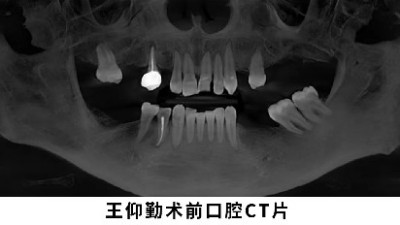

经检查发现,王女士30岁左右就出现了牙齿脱落现象,还有5颗牙只剩下残根、牙体变色,不仅影响美观,还丧失了咀嚼功能。此外,她还患有重度牙周炎、龋齿、根尖周炎等疾病,不仅牙龈红肿,有几处还出现了脓包,轻轻一按就会溢出黄色脓液。

为她诊治的王宏峰博士说道:“患者从小就爱吃糖,且口腔卫生条件差。糖会产生酸性物质,促进细菌滋生、腐蚀牙齿,这才诱发龋齿、牙周炎、根尖周炎等疾病。后牙的长期缺失,使得邻牙往前倾斜、松动;尤其是左上部位,因长期缺牙导致骨量非常不足。”

在全面评估了王女士的口腔情况之后,王宏峰博士决定为她进行牙周刮治、龋齿修补和种植牙修复手术。他拔除了一些无法保留的残根,并根据剩余的骨量情况进行种植牙手术,特别是在骨量严重不足的前牙区域,进行了上颌窦提升及骨增量手术。